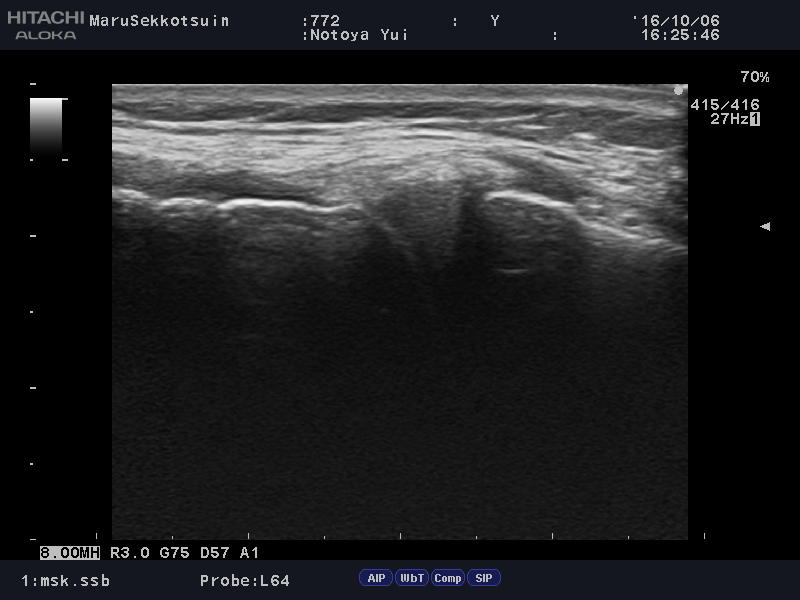

いつものように問診して、触診して、エコー検査。

結果「膝の内側側副靭帯」の損傷

内側の半月板も怪しいですが、

こちらの患者様、半月板の損傷も疑われ、

患部の状態をしっかり把握しながら治療をするため、

膝専門のドクターをご紹介させて頂きました。